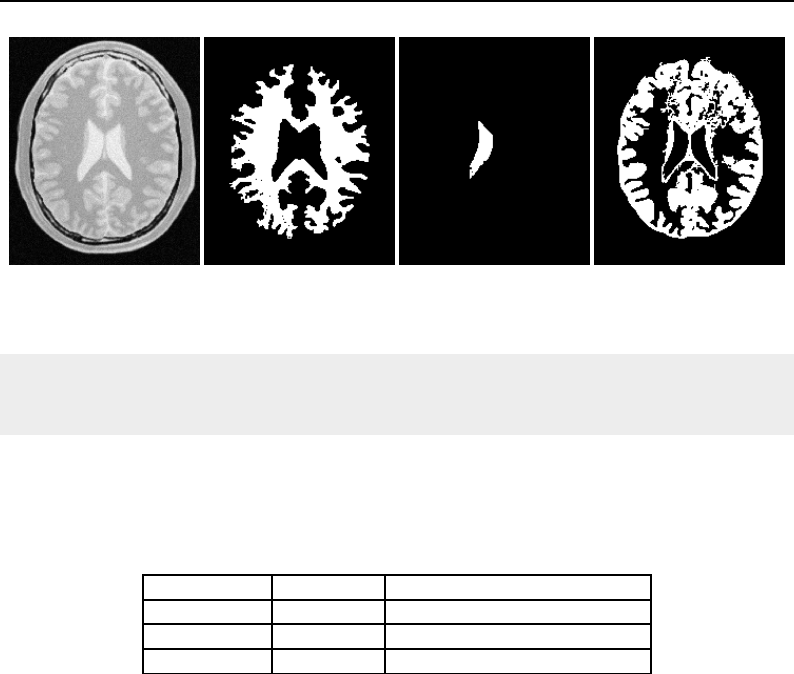

The National Library of Medicine Insight Segmentation and Registration Toolkit, shortened as the

Insight Toolkit (ITK), is an open-source software toolkit for performing registration and segmenta-

tion. Segmentation is the process of identifying and classifying data found in a digitally sampled

representation. Typically the sampled representation is an image acquired from such medical instru-

mentation as CT or MRI scanners. Registration is the task of aligning or developing correspondences

between data. For example, in the medical environment, a CT scan may be aligned with a MRI scan

in order to combine the information contained in both.